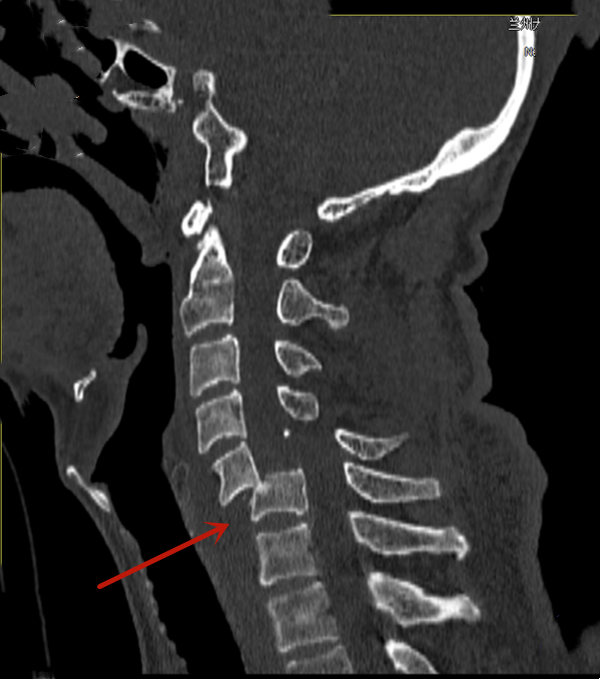

术前影像资料

患者男性,66岁,不慎滑倒后从1米高台阶处跌落摔伤,颈部着地,颈部疼痛难忍并伴有双上肢麻木等症状,紧急入院,给予对症处置后行颈椎X线片、三维CT、MRI及颈部血管CTA等辅助检查,结合检查检验结果,诊断为创伤性颈椎骨折脱位、颈髓损伤、颈6椎体骨折、颅脑损伤。经科室讨论评估后,于2月21日由急救中心副主任成鹏在全麻下成功实施颈椎前路切开复位、C5/6椎间植骨融合、前路钢板内固定术+颈椎后路螺钉系统内固定术,术后恢复良好,四肢肌力恢复正常,现已康复出院。本例手术的成功救治,标志兰大二院急诊外科在严重、复杂脊椎创伤救治方面又上了新台阶。